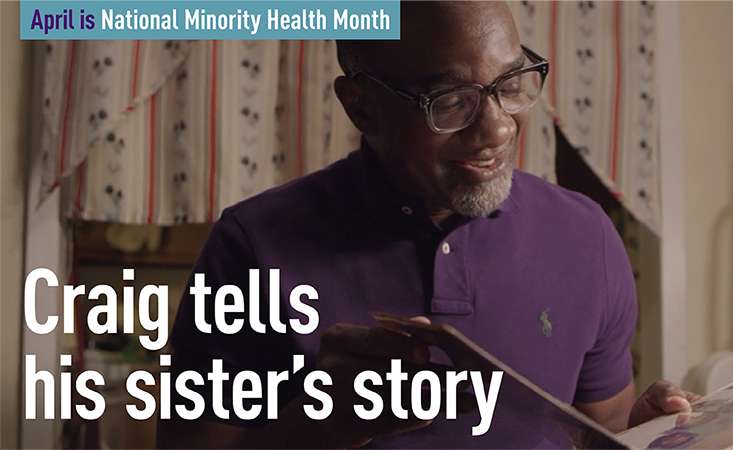

After losing his sister to pancreatic cancer, Craig Irving is focused on educating the Black community about symptoms of the disease and the importance of clinical trials.

Craig Irving

PanCAN supporter

Corporate Sales Manager, Eastern Division, American Airlines

Craig was a caregiver for his sister, whom he lost to pancreatic cancer